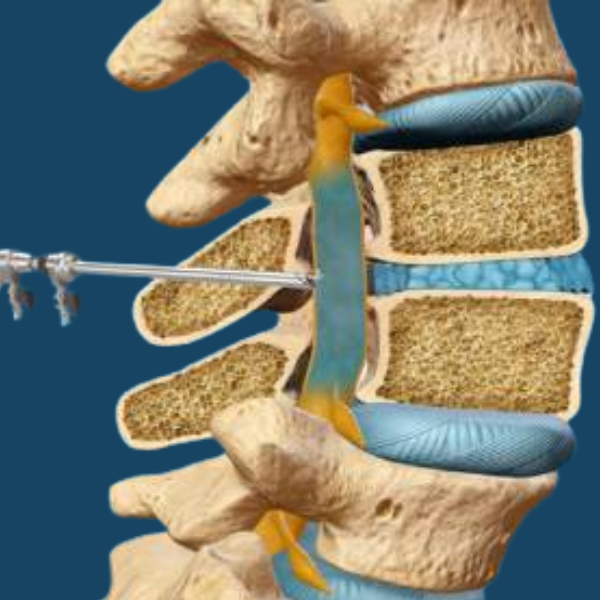

Minimally Invasive Spine Surgery

Minimally invasive spine surgery uses small incisions and advanced techniques to treat conditions like herniated discs, spinal stenosis, and degenerative disc disease. This approach reduces recovery time and minimizes risk, allowing patients to return to their daily activities faster.